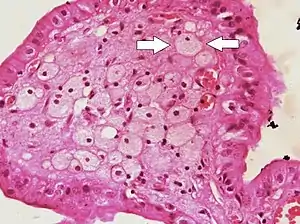

|  Foam cells (one indicated by arrows) visible in the finger-like projections into the gallbladder lumen in a case of cholesterolosis | |

Foam cells are fat-laden M2 macrophages containing low density lipoproteins (LDL). They can only be truly detected by examining a fatty plaque under a microscope after it is removed from the body.[4] They are named because the lipoproteins give the cell a foamy appearance.[5]